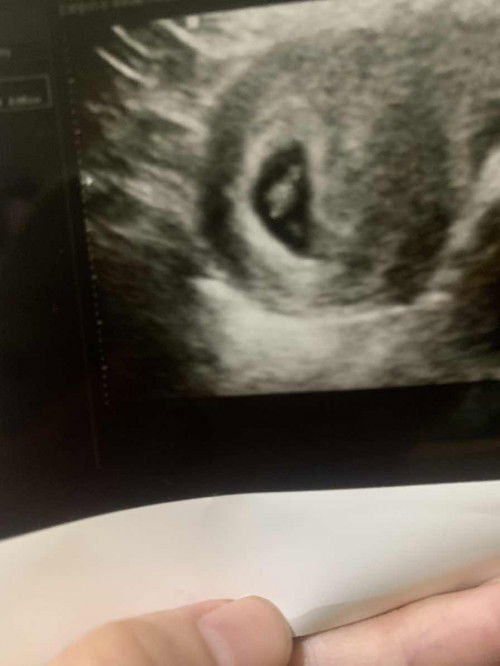

Ada pendarahan di bawah kantung kehamilan

Mau tanya dong mom, ada gak ya yang hamil muda di trimester 1 pas di USG ada pendarahan dibawah kantung kehamilannya? Janinnya si sudah berdenyut di 6w1d.. Ini si disuruh gak boleh capek-capek dan tetep lanjutin minumin microgestnya kata obgynnya.. Tapi tetep khawatir.. Padahal gak ada flek/kram cuma kemaren itu memang 2 kali kayak berasa ada sakit sedikit kayak ditusuk.. #ingintahu #pleasehelp